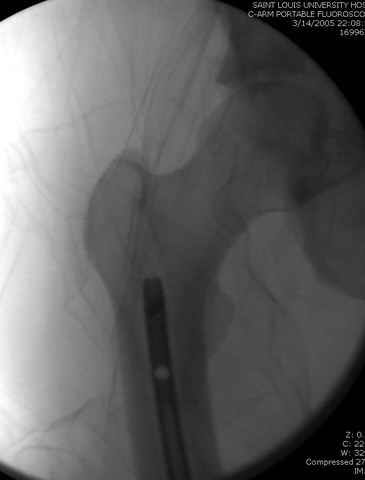

По поводу открытого перелома больной ургентно взят на ретроградное интрамедулярное штифтование, после рутинного дебрайдмента и фасциотомии на бедре и на голени.

перелом бедра

интраоперационные